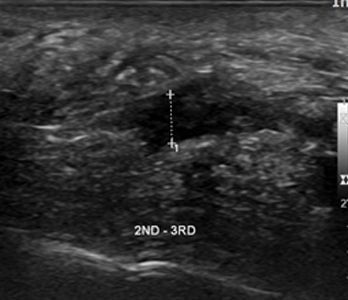

남성 지간신경종